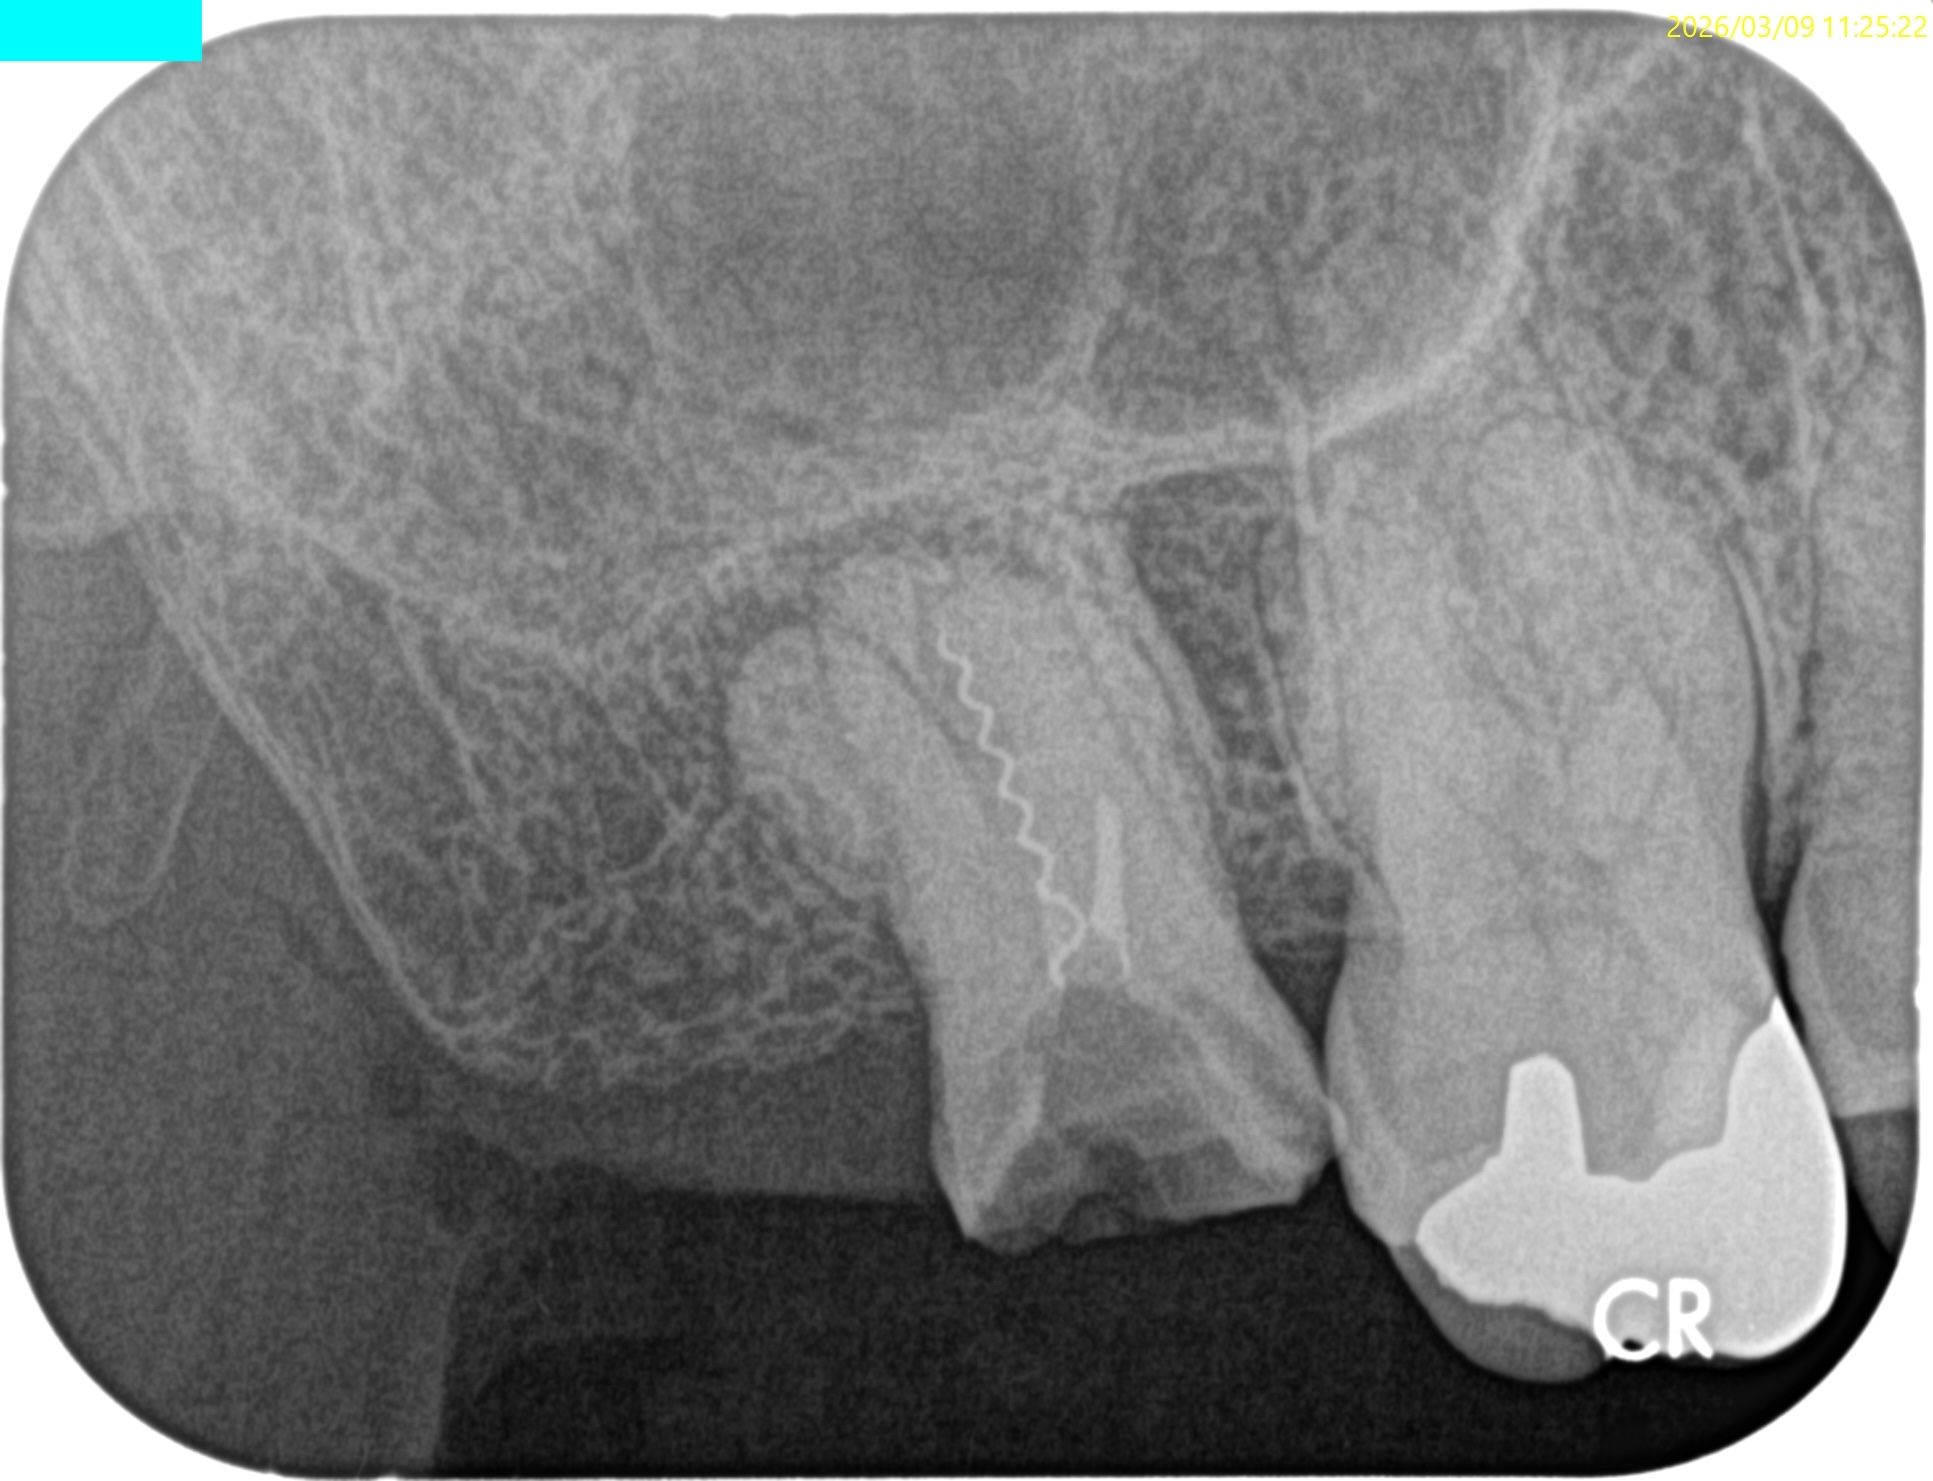

Pre-op Endo test(2026.3.9)

#2

MB, DB, Pともに石灰化している。

DBは根管口自体がどこにあるか?判然としない。

予測では、

MBのGutta Percha Pointの近傍にそれはありもしかすると石灰化しているかもしれない。

その際は3mm~4mm程度削合する必要があるかもしれない。

また、Pはレンツロが破断してしまい、前医(紹介歯科医院ではない)は知らん顔している。

根尖病変があり頬側歯槽骨が穿孔しているDB, レンツロが破断しており根尖病変があるPをSelectiveに再根管治療するという方針を術前に決定した。

Pre-op Endo Diagnosis(2026.3.9)

Pulp Dx: Previously initiated therapy

Periapical Dx: Symptomatic apical peridontitis

Recommended Tx: Re-RCT

根管充填後にPA, CBCTを撮影した。

DB

P

問題はないだろう。